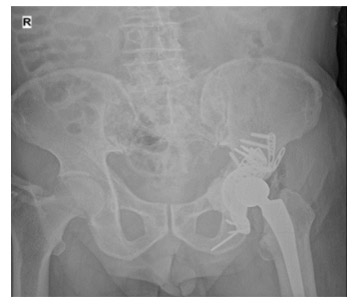

Post-surgery: The X-ray shows a total hip replacement implanted with acetabulum cemented with a titanium plate and ring.